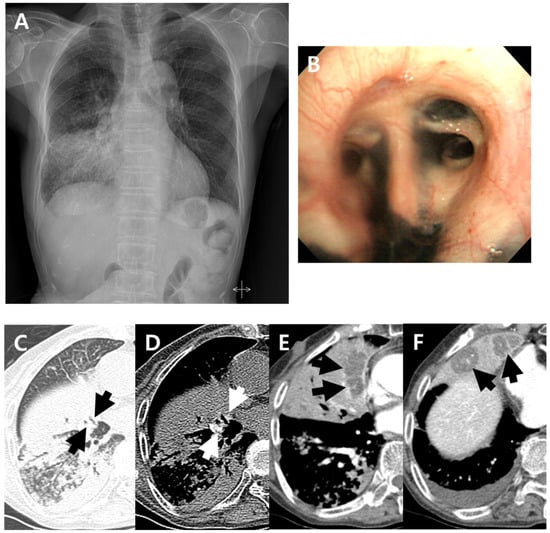

Figure 1.

A 79-year-old woman with pulmonary tuberculosis and underlying bronchial anthracofibrosis presented with an abnormal chest plain radiograph. (A) Chest plain radiograph showed consolidation and ill-defined nodular opacities in right lower lung field with lower lobe predominance. (B) Bronchoscopic image showed luminal narrowing at segmental bronchi of right middle lobe with multifocal deposition of black pigmentation, and bronchial anthracofibrosis was diagnosed. (C,D) Non-enhanced axial CT scan showed bronchostenosis (black arrows) at medial and lateral segmental bronchi of right middle lobe and peribronchial hyperattenuation (white arrows) around medial and lateral segmental bronchi of right middle lobe. These CT findings suggested bronchial anthracofibrosis. (E,F) Contrast-enhanced axial CT scan showed internal low-density areas (arrows) within atelectasis of right middle lobe. These findings were atypical CT findings of pulmonary tuberculosis, which cannot be suspected of TB. By the way, clustered micronodules with tree-in-buds and consolidations in right lower lobe were shown on the axial CT scan which were well known typical CT findings of pulmonary tuberculosis. CT = computed tomography.